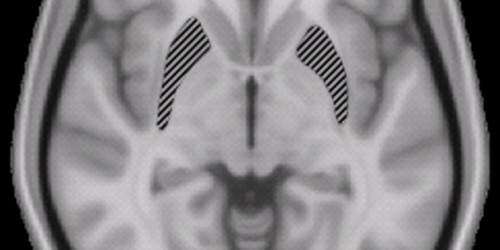

Ello es corroborado por un reciente estudio publicado en la revista PloS One y llevado a cabo por la Universidad de Cambridge (Inglaterra), que reveló que el cuerpo estriado o núcleo estriado -que juega un papel importante en el centro de recompensa del cerebro- se iluminaba igualmente cuando se trataba de alcohólicos como de adictos al porno al mostrarles imágenes de su objeto de deseo.

Los científicos descubrieron que tres regiones concretas del cerebro eran mucho más activas en las personas adictas a estos contenidos sexuales: el cuerpo estriado, la corteza cingulada anterior (control ejecutivo, control emocional) y la amígdala (centinela de las emociones).

Además, ver demasiada pornografía también modifica el tamaño de nuestro cerebro. En otro estudio llevado a cabo por el Instituto Max Planck (Alemania), los investigadores descubrieron que el volumen del cuerpo estriado del cerebro disminuía cuanto más imágenes sexuales explícitas se veían.

‘Hemos encontrado un importante vínculo negativo entre el acto de ver pornografía varias horas a la semana y el volumen de materia gris en el lóbulo derecho del cerebro, así como la actividad de la corteza prefrontal’, explicaban los autores del estudio.